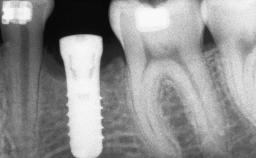

A 20-year-old woman was referred for implant therapy in 2004. Her medical history revealed no significant findings, and neither did she smoke nor take any medications. An extraoral examination revealed no abnormalities of the skin, hair or nails. The intraoral examination revealed only 11 permanent teeth clinically. These were normal in shape, size, and color. In addition, eight retained deciduous teeth (53, 62, 63, 71, 72, 73, 81, 82) were present. No abnormalities were detected during the general examination. The family history revealed that the patient’s father and two sisters were on record with similar conditions. The clinical examination revealed a thick gingival biotype. No recession of the attached gingiva was noted, but the retained deciduous teeth were mobile and unsightly. As a syndrome had not been diagnosed, the case was categorized as non-syndromic oligodontia.

| Bone Volume | Deficient horizontally, requiring prior grafting |